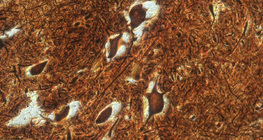

300 дахин томруулсан